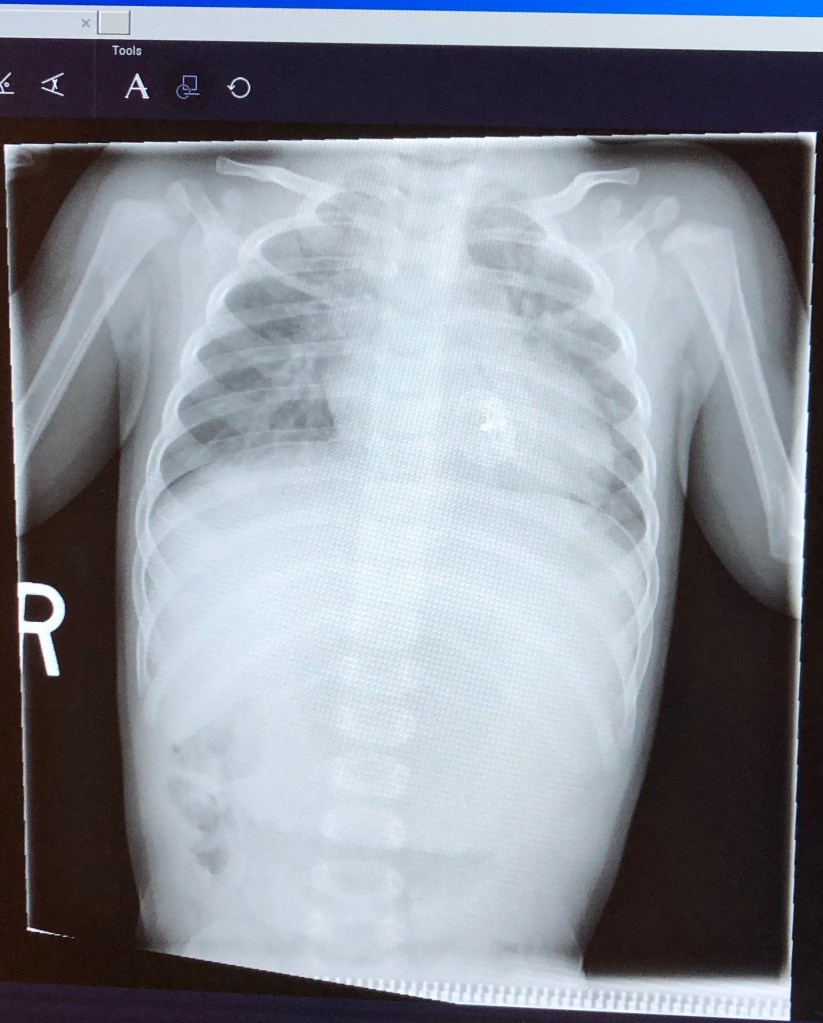

At her most recent cardiology check-up, she had the most endearing expression of determination and courage on her face through an x-ray, EKG, and echo. And her heart is looking good. She will have annual check-ups for another few years and then the hope is that they become less frequent.